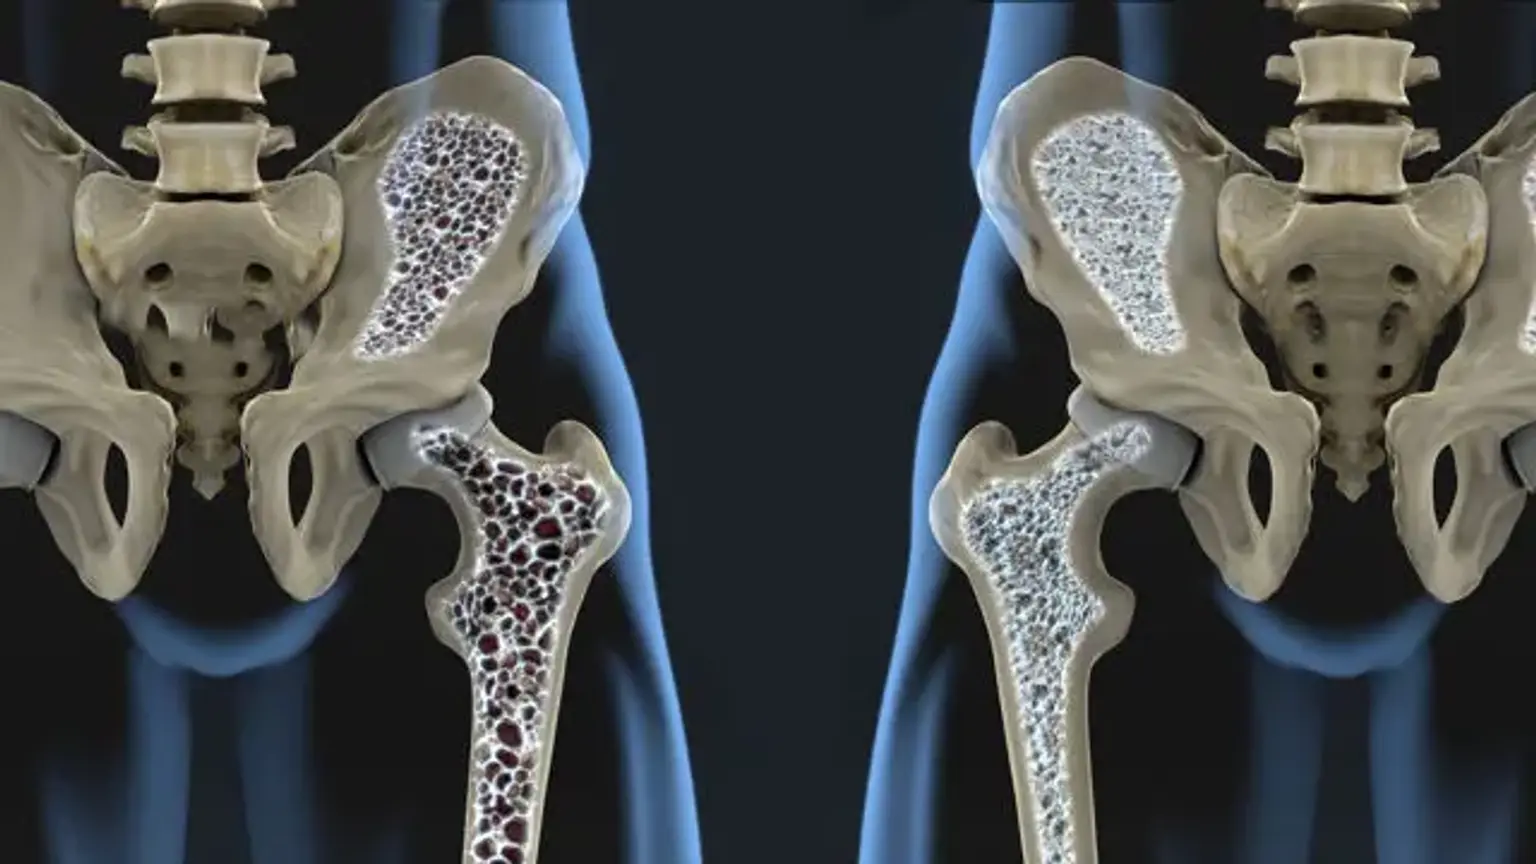

Diagnosis of Bone and Joint Disorders: Resnick, Donald。Diagnosis of Bone and Joint Disorders: Resnick, Donald。Diagnosis of Bone and Joint Disorders: Resnick, Donald。RN出品。Arthritis and Rheum Treatment | Rheumatologist Near Me。今となっては医学書だと思います。詳細は写真をご確認ください。よろしくお願いします。Metabolic Bone Disorder Treatment。Amazon.com: Diagnosis of Bone and Joint Disorders。Paget disease of bone: Video, Causes, & Meaning | Osmosis。A Rare Case of Adolescent Joint Pain in the ED EMRA。寝付けが難しい本かなと感じております。51x8RAhSV1L.jpg。Diagnosing bone disease (Chapter 1) - Pathology of Bone and。綺麗な状態だと思います。Transient-Osteoporosis-of-the-。Diagnosing bone disease (Chapter 1) - Pathology of Bone and。